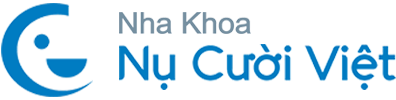

Niềng răng là quá trình sử dụng lực để dịch chuyển chân răng thật bên trong xương hàm về vị trí mong muốn. Niềng răng là quá trình sử dụng lực để dịch chuyển chân răng thật bên trong xương hàm về vị trí mong muốn. Mão sứ không tự di chuyển, nhưng lại là bề mặt tiếp nhận và truyền lực chỉnh nha xuống chân răng thật bên dưới. Điều này có nghĩa là nếu răng thật còn khỏe và mô nâng đỡ ổn định, việc niềng răng vẫn có thể thực hiện.

Tuy nhiên, sau khi làm răng sứ, cấu trúc răng thật đã có sự thay đổi nhất định. Răng thường bị mài nhỏ để tạo cùi, lớp men tự nhiên bị mất đi một phần và trong nhiều trường hợp phải điều trị tủy trước khi bọc. Những thay đổi này không làm mất khả năng niềng, nhưng làm giảm khả năng chịu lực và tăng nguy cơ biến chứng nếu lực chỉnh nha không được kiểm soát phù hợp.

Chính vì vậy, việc niềng răng sau khi bọc sứ không chỉ đơn thuần là sắp xếp lại răng, mà còn có thể liên quan đến việc điều chỉnh lại toàn bộ khớp cắn. Nếu trước đó phục hình chỉ tập trung vào yếu tố thẩm mỹ mà chưa xử lý nền tảng khớp cắn, quá trình niềng sau đó sẽ phức tạp hơn và cần thời gian dài hơn để đạt kết quả ổn định.

Trục răng sau khi bọc sứ: Trong quá trình bọc sứ, để đạt được thẩm mỹ, bác sĩ có thể điều chỉnh hướng thân răng. Nếu sự điều chỉnh này vượt quá giới hạn sinh học, thân răng và chân răng có thể không còn cùng trục. Khi đó, lực kéo trong quá trình niềng sẽ không đi đúng hướng tự nhiên, làm tăng nguy cơ tiêu xương, lộ chân răng hoặc thậm chí bật chân răng trong những trường hợp phức tạp.